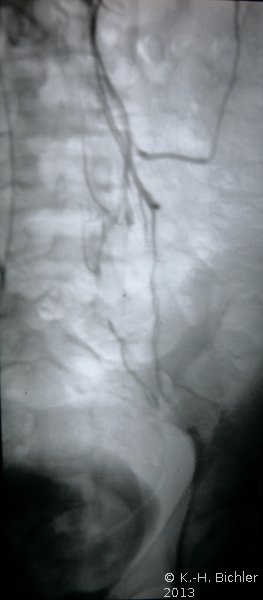

Bei dem 20 Jahre alten Mann fand sich eine Anorchie. Zur Abklärung wurde eine retrograde Venographie, ausgehend von einer Punktion der Vena femoralis (via Vena renalis sinistra) durchgeführt. Durch Sondierung und Kontrastmittelgabe konnten zwei filiforme Abgänge nach distal aus der Vena renalis sinistra dargestellt werden. Eine Sondierung zeigte multiple Gefäße, die sich bis in die Linea terminalis des Beckens verfolgen ließen. Vom Verlauf dieser Gefäße her ist anzunehmen, dass es sich bei einem davon um die linksseitige Vena testicularis handelt (Abbildung 1). Die Sondierung der rechten Testicularvene gelang nicht. Laparoskopisch konnten keine Hoden bzw. entsprechendes fibröses Gewebe gefunden werden. Auch bei einer Computertomographie des Abdomens und des Beckens fand sich kein Anhalt für Hodengewebe beiderseits.

Zusammenfassend fand sich ein von der Vena renalis sinistra abgehendes Gefäßkonvolut, bei dem es sich vom Verlauf her um die Vena spermatica interna handeln könnte. Rechts fand sich keine Vena testicularis. Laparoskopie und CT ergaben keinen Anhalt für Hodengewebe.